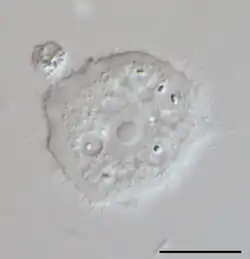

| Phase contrast micrograph of an Acanthamoeba polyphaga cyst. | |

Acanthamoeba is a genus of amoebae that are commonly recovered from soil, fresh water, and other habitats. The genus Acanthamoeba has two stages in its life cycle, the metabolically active trophozoite stage and a dormant, stress-resistant cyst stage. In nature, Acanthamoeba species are generally free-living bacterivores. However, they are also opportunistic pathogens able to cause serious and potentially fatal infections in humans and other animals.[1]